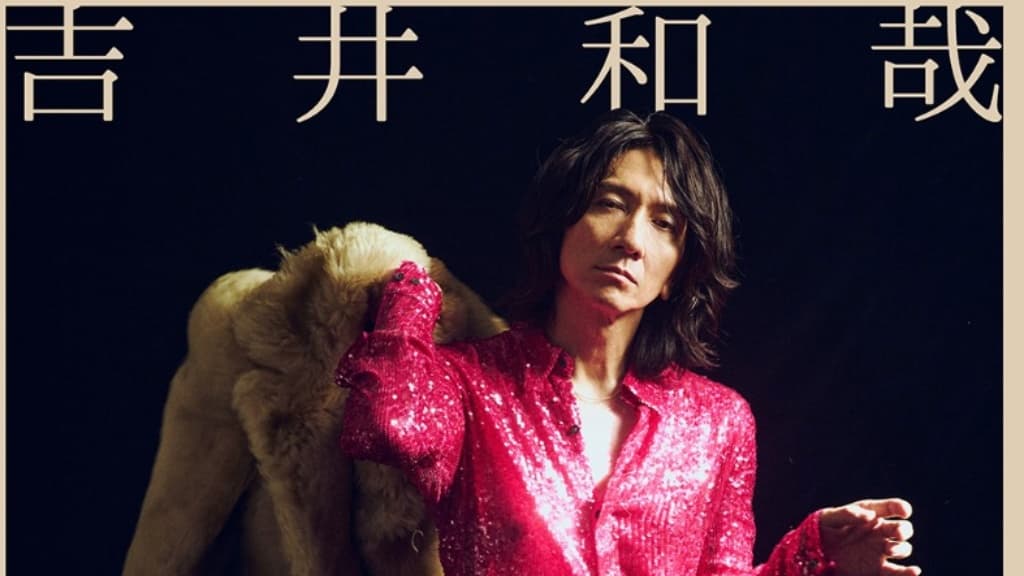

活躍日本歌壇逾30年的搖滾樂團「THE YELLOW MONKEY」主唱吉井和哉驚傳罹癌,57歲的他透過官網公開罹患喉頭癌的消息。據了解他去年因為發炎發現喉頭息肉,去年2月切除息肉後一直不滿意歌唱水準,9月和10月分別再切除息肉,11月發現早期喉頭癌。醫師表示,喉頭癌在咽喉癌中算幸運的,因為病灶侷限在喉返軟骨內,早期發現不易轉移,但要戒菸酒並每個月追蹤,避免復發。

吉井和哉3度切除聲帶息肉 後發現早期喉癌

吉井和哉表示,他前年12月結束武道館個別演唱後就感覺不適,分別在去年2月、9月和10月進行3次切除手術,經過戒聲期開始練唱時,他發現喉嚨疑似長腫瘤,11月醫師確認為早期喉頭癌。醫師說明治療3個月可根治,他也馬上接受治療,今年初已經順利根治。他很開心能早期發現腫瘤,但因為認為聲音尚未回復可以上台表演的水準,因而取消年底的演唱。

▲吉井和哉在官網上公開罹癌和治療經過,並取消年底的單飛20周年演唱會。(圖片/翻攝自吉戒和哉Twitter)